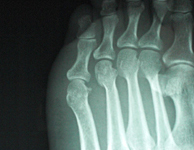

| マレットフィンガーDrに依頼施療中 | 同患者のレントゲンDr依頼により当院にて施療 | ||